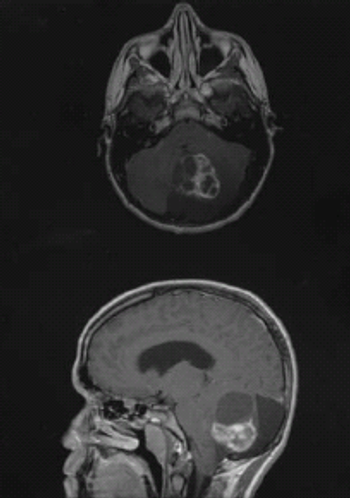

The recommended dose of ceritinib once daily with food demonstrated promising preliminary clinical activity in patients with ALK-positive relapsed/recurrent inflammatory myofibroblastic tumors and anaplastic large cell lymphoma, and certain subsets of relapsed/refractory neuroblastoma.